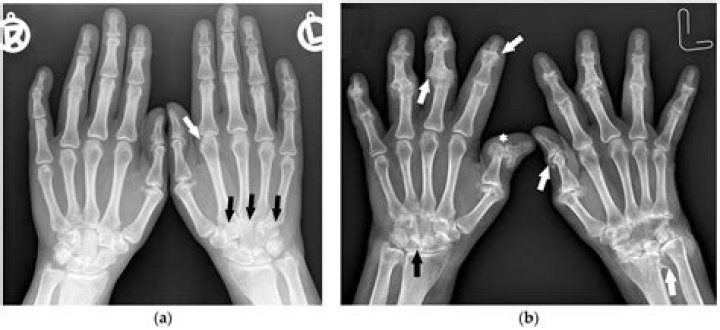

There is no single test for diagnosing osteoarthritis, but often it is diagnosed by an abnormal X-ray that shows characteristic features such as narrowing of the joint and spurring of the joint margins. Your doctor will take your medical history and perform a physical examination.